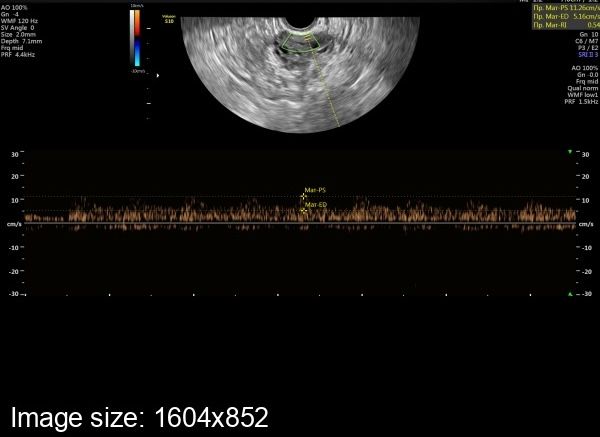

Объективно - по индексу резистентности.В сосудах нормального желтого тела снижение ИР в среднем до 0,44 происходит на 2 день после овуляции. И это значение не меняется в течение первых 5 дней второй фазы.

За неделю до месячных ИР повышаеся в среднем до 0,47 и затем постепенно увеличивается в среднем до 0,53 к концу менструального цикла.